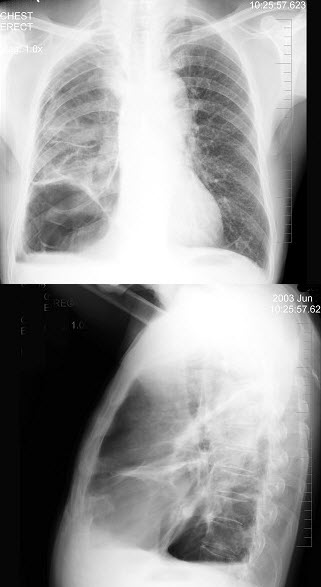

3、单项选择题

男,74岁,咳嗽,咳痰1月余,咯血丝痰1周伴胸痛,胸片如图,最可能的诊断为()

A.右上肺浸润型肺结核

B.右上肺不张

C.右侧中央型肺癌并右上肺不张

D.右侧包裹性积液

E.右肺上沟瘤

47、单项选择题

男,6岁。经常咳嗽、憋喘,呼吸急促、口唇青紫,进行性加重。X线检查如图,最可能的诊断为()

A.先天性PDA

B.先天性VSD

C.先天性ASD

D.法洛氏四联症

E.先天性肺动静脉瘘

112、单项选择题

男,54岁,咳嗽,伴胸痛2周,午后有低热,胸片如图,最可能的诊断是()

A.肺脓肿

B.结核空洞

C.韦格肉芽肿

D.肺癌

E.肺大泡

126、单项选择题

女,12岁,咳嗽、低热2月余,结合胸片,最可能的诊断是()

A.血行播撒型肺结核

B.两肺含铁血黄素沉着

C.间质性肺炎

D.支气管肺炎

E.风心二狭